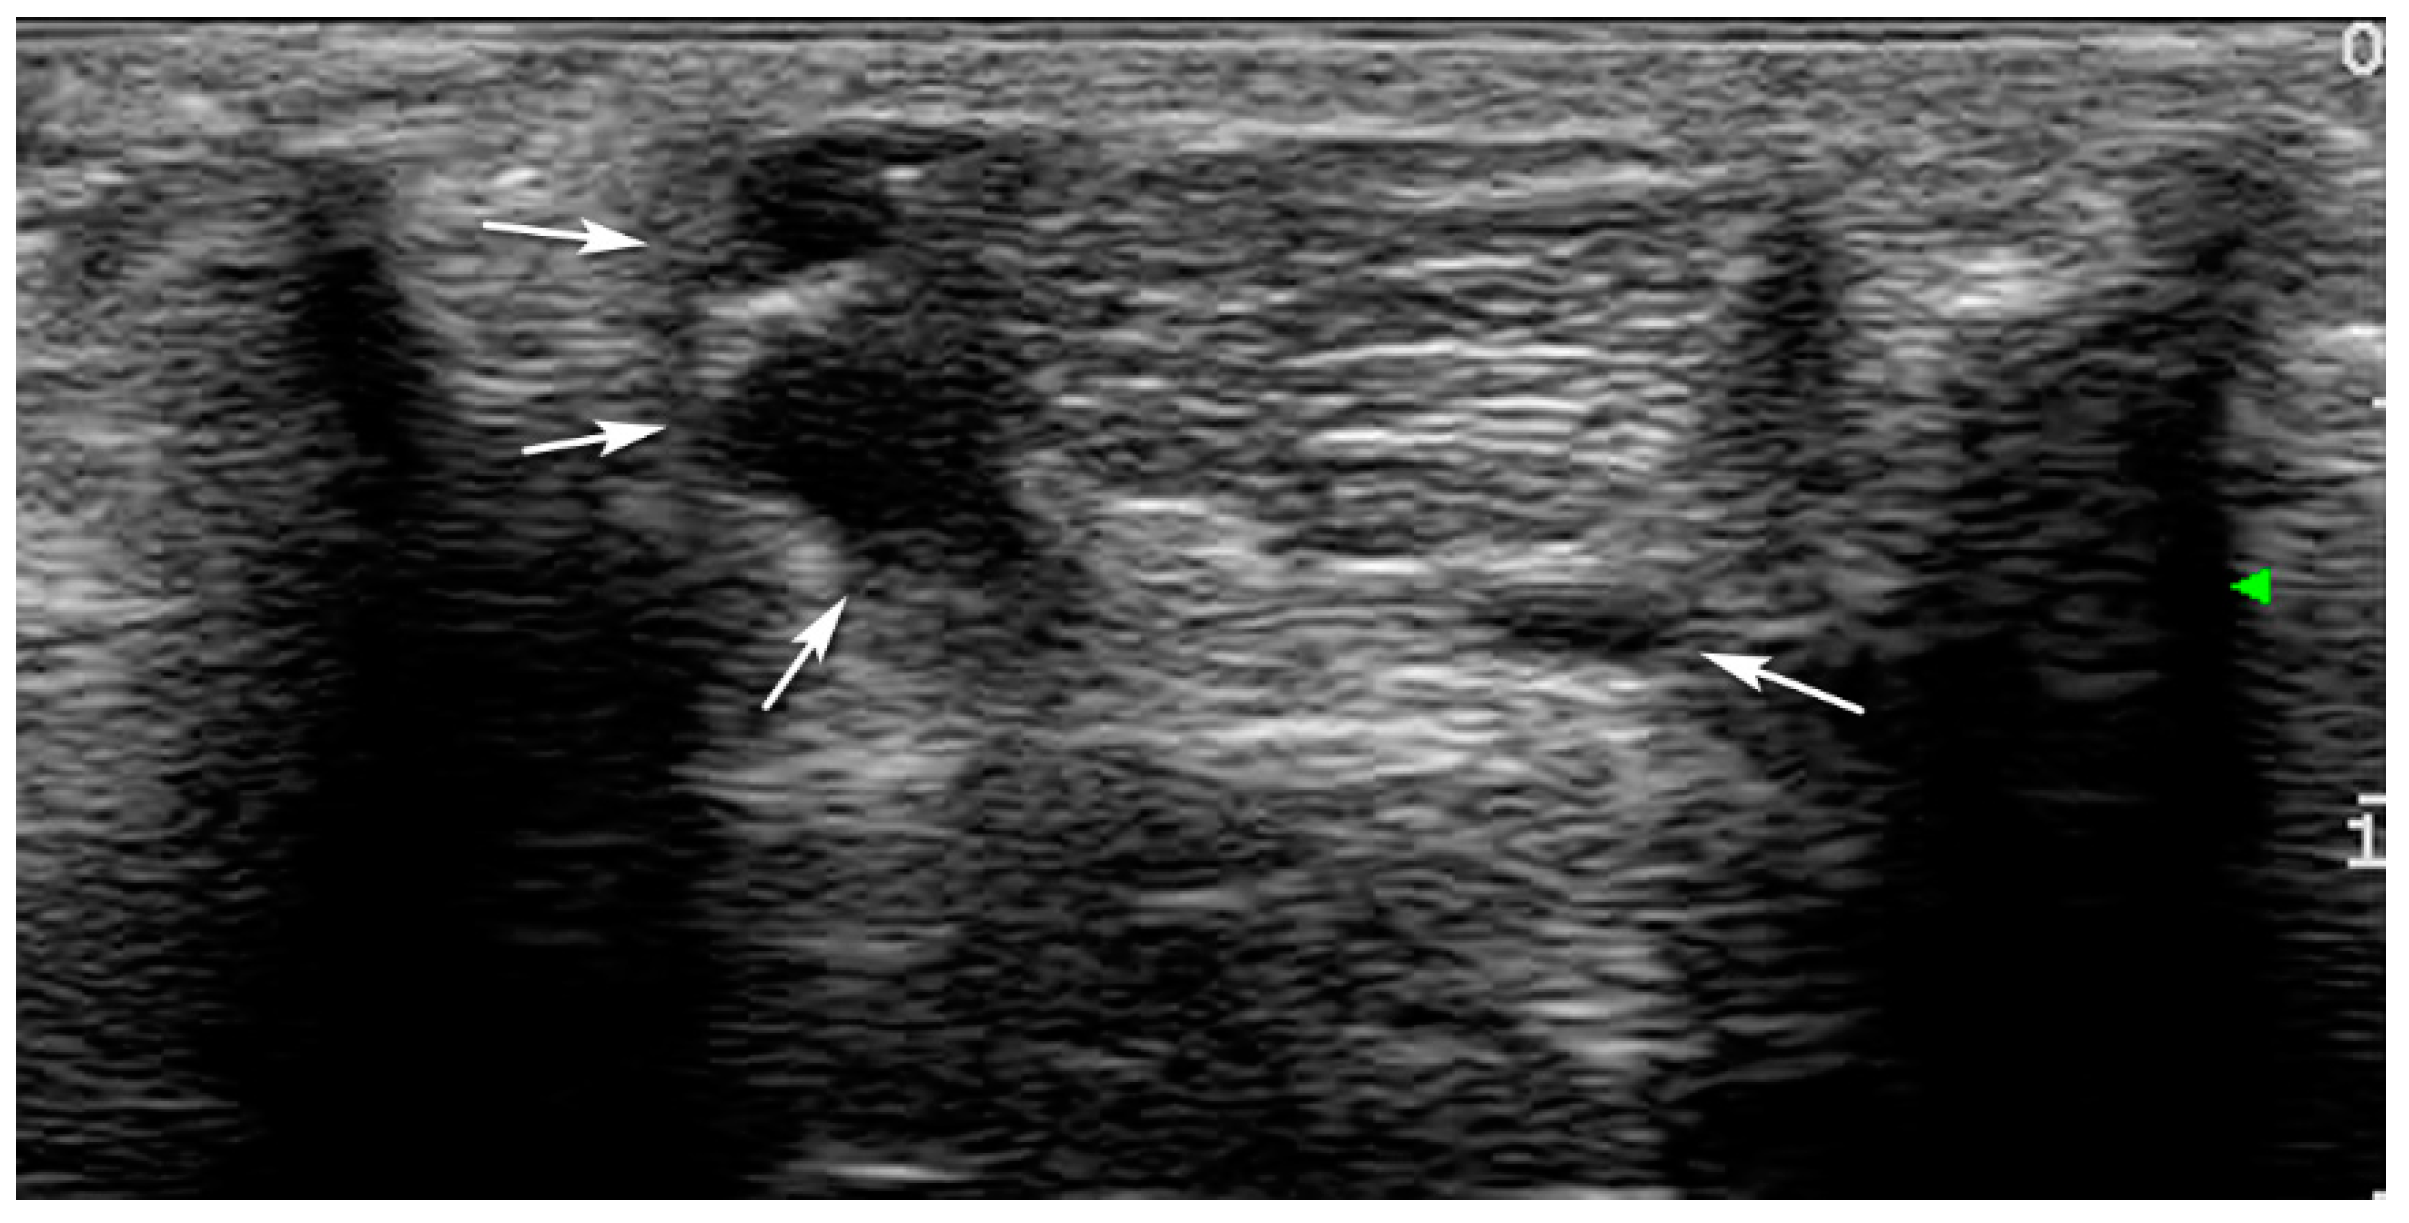

- Grade 1: Normal tendon with parallel fibers and homogeneous architecture

- Grade 2: Enlarged tendon with bowed margins and homogeneous architecture

- Grade 3: Hypoechoic area with or without tendon enlargement and bowed margins